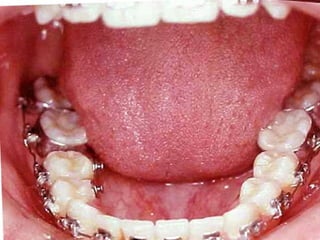

Arcada Superior: Forma oval Paladarprofundo Totalidad de órganos dentarios a excepción de tercer molar izq. Restauraciones deficientes Arcada Superior: Forma oval Paladar profundo Totalidad de órganos dentarios a excepción de tercer molar izq. Restauraciones deficientes Frente: Línea media desviada Mordida cruzada anterior Frente: Línea media desviada Mordida cruzada anterior Arcada Inferior: Forma ovalada Colapso posterior Ligero apiñamiento de anteriores Rotación de premolares Arcada Inferior: Forma ovalada Colapso posterior Ligero apiñamiento de anteriores Rotación de premolares